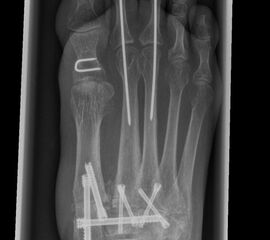

Die Korrektur des Spreizfußes und die Stabilisierung des TMT I ist das zentrale Element zur Entlastung des TMT II und III Gelenks. Dadurch kann die Lastachse wieder auf den ersten Strahl geführt werden. Aus Gründen der Stabilität sollte die Indikation zu einer Lapidusarthrodese großzügig gestellt werden. Eine TMT II und ggf. TMT III Arthrodese wird dann unter Berücksichtigung des Metatarsalindex unter Längenerhalt oder leichter Kürzung durchgeführt. Beim Pes metatarsus adductus kann der Eingriff mit einer Achskorrektur durchgeführt werden, um die Adduktionsstellung des Mittelfußes zu korrigieren (Abb. 9 und 10).

Zum Lesen der Bildbeschreibung und zur Vollansicht bitte die Bilder anklicken. Bilder: C. Hase

Es gibt neben der Möglichkeit mit der in situ TMT II, III Arthrodese auch die Möglichkeit Fehlstellungen wie den Pes metatarsus adductus zu adressieren (Abb. 9 und Abb. 24 zeigen das prä- und postoperative Röntgenbild eines Patienten mit Pes adductus Korrektur).

Zum Lesen der Bildbeschreibung und zur Vollansicht bitte die Bilder anklicken. Bilder: C. Hase.

• Röntgenkontrolle nach 8-10 Wochen, dann - je nach knöchernem Durchbau - Übergang zur Vollbelastung im Konfektionsschuh (Abb. 24 und 25).